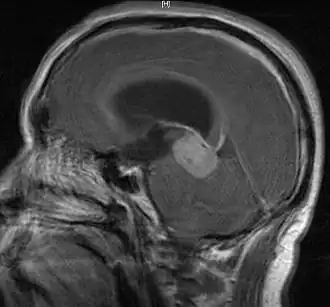

Germinoma extragonadal

Resonancia magnética del sistema nervioso central mostrando un germinoma. Véase también el corte transversal. | ||

Un germinoma es un tipo de tumor de células germinales no diferenciado histológicamente.[1] Pueden ser tumores malignos o benignos y se localizan con mayor frecuencia en el cerebro donde tienen características muy similares a los disgerminomas del ovario y los seminomas de los testículos.[2] Desde 1994, el Medical Subject Headings ha definido a un germinoma como una neoplasia maligna del tejido germinal de las gónadas, mediastino y de la región pineal.